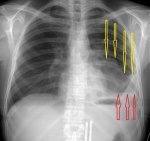

Это контур чего (желтые стрелки)?

2013_83toraks._kray.jpg

я думаю желтые стрелки указывают на край коллабированной доли легкого, а жидкость ни что иное как кровь. а данных за пневмоторакс не нахожу.

Интересно, какой доли?